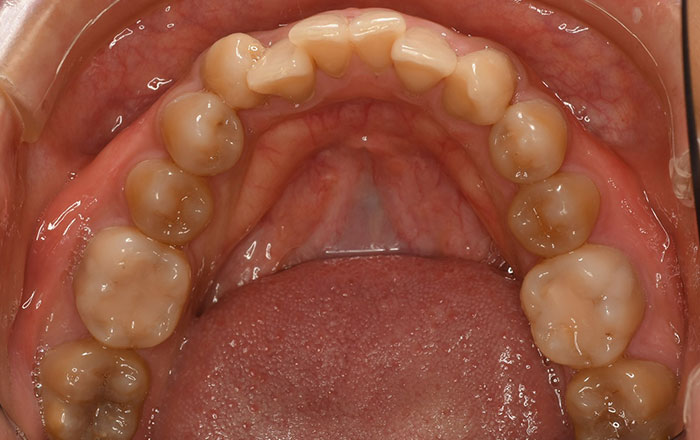

3.エナメル質が薄くなった事による変色

・歯の磨きすぎ

・歯ぎしり

・加齢

などで、歯のエナメル質が薄くなり、内側の象牙質が透けて見える場合も、黄みがかった歯となります。

加齢により、歯はエナメル質が薄く、象牙質が厚くなるため全体的に黄色くなっていきます。

この場合は、ホワイトニングで改善できます。